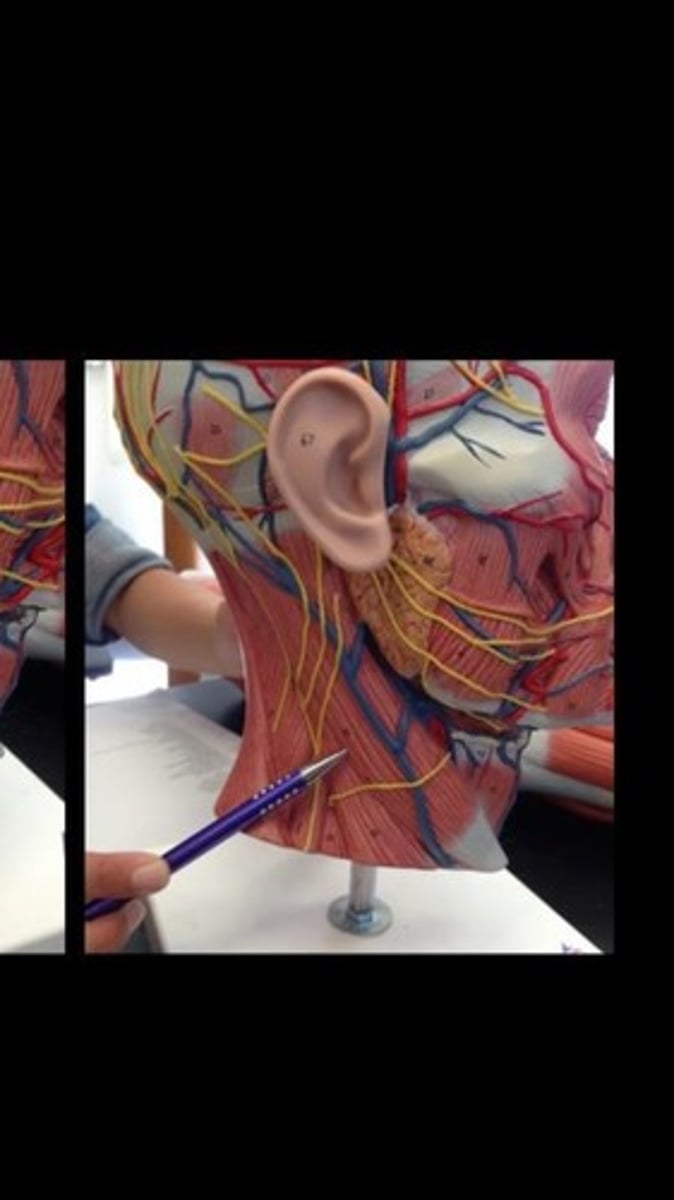

Sternocleidomastoid